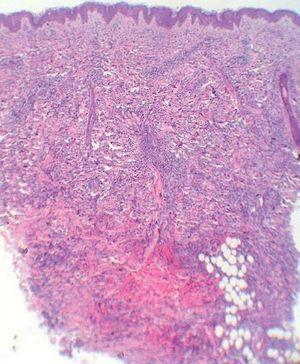

Cinco días más tarde, las lesiones cefálicas y troncales se habían reducido notablemente sin tratamiento, pero habían aparecido numerosas pápulas en los miembros. Al inicio y durante el seguimiento le practicamos varias analíticas generales, una radiografía de tórax y una ecografía abdominal que estaban dentro de la normalidad. El estudio histopatológico de un punch profundo mostraba un infiltrado dérmico superficial y profundo, de predominio perivascular, que se disponía en fila disecando los haces de colágeno (fig. 3). La epidermis estaba respetada y la dermis presentaba una zona grenz libre de tumor. El infiltrado estaba formado por células de aspecto indiferenciado, de núcleos grandes e hipercromáticos y con numerosas mitosis atípicas. Inmunohistoquímicamente las células mostraban positividad para mieloperoxidasa, lisozima, CD43 y CD68, siendo negativas para CD56, TCLI, CD123, TdT, CD30, CD3, CD20, S100, CD1a y CD34. Con estos hallazgos se realizó el diagnóstico de leucemia cutis (LC), concretamente de cloroma, o infiltración por sarcoma mieloide o granulocítico.

Figura 3. Infiltración celular densa e infiltrante en dermis y tejido celular subcutáneo. (Hematoxilina-eosina, x4.)